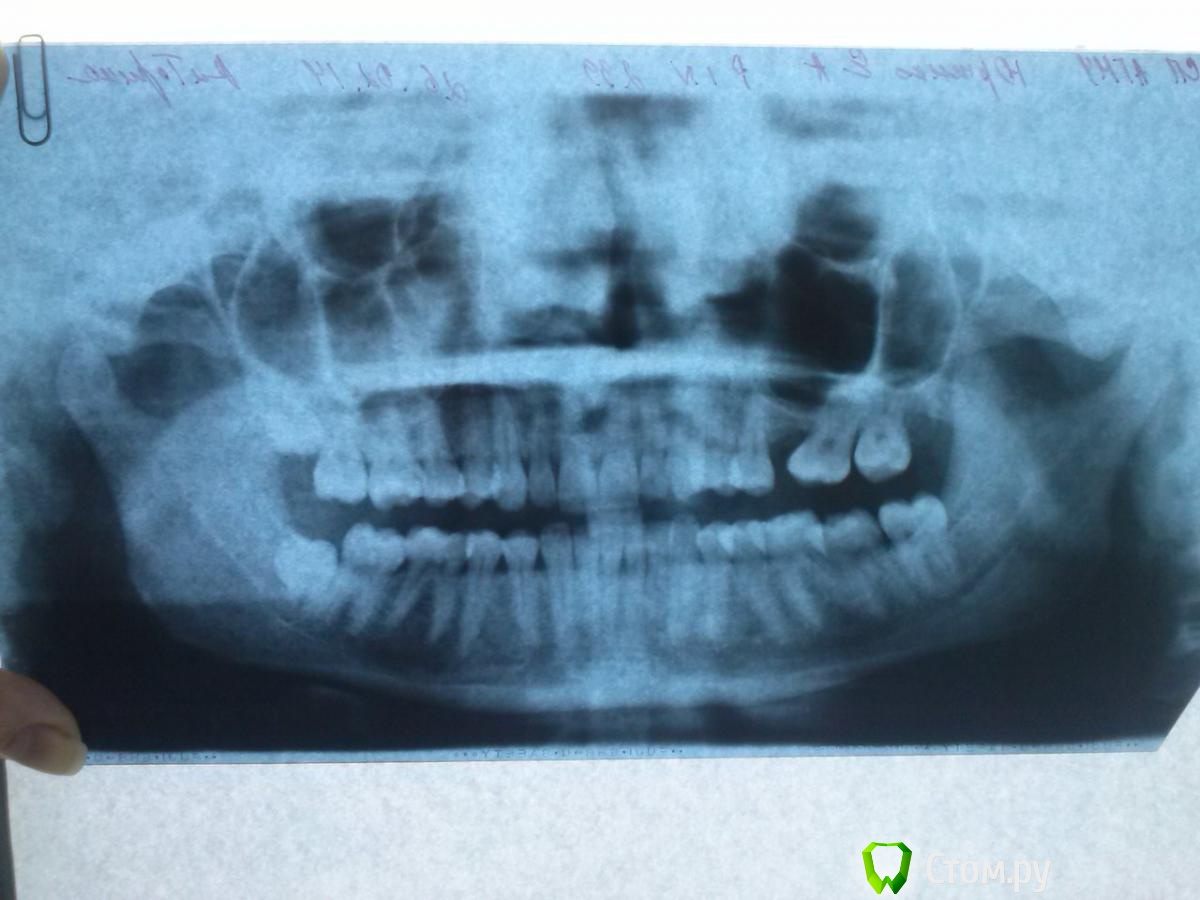

makemake Опубликовано 12 октября, 2014 Поделиться Опубликовано 12 октября, 2014 Здравствуйте.Мне 26 лет, 6ку удаляла в 15,хочется узнать до начала ортодонтического лечения:возможно ли ставить имплант или только мост?(ортодонт говорит,что есть вероятность,что костная ткань нарастет в процессе лечения) Предлагает удалить 8ку справа сверху. Сдвинуть 7ку и освободить место для моста или импланта. Снизу удалить восьмерку и вернуть в начальное положение нагнувшийся нижний зубной ряд справа. Ссылка на комментарий

makemake Опубликовано 13 октября, 2014 Автор Поделиться Опубликовано 13 октября, 2014 Хотя бы подскажите,хватит ли костной ткани для имплатна или можно подтянуть 7 и 8 к 5ке?? Не хочу я мост((( Ссылка на комментарий

IvanK Опубликовано 13 октября, 2014 Поделиться Опубликовано 13 октября, 2014 Здравствуйте, не хватит, синус-лифтинг, как минимум, потребуется я бы предложил удалить все 8ки, 7ку вернуть на место с помощью ортодонта либо оставить все как есть... 3 Ссылка на комментарий

makemake Опубликовано 13 октября, 2014 Автор Поделиться Опубликовано 13 октября, 2014 Синус-лифтинг ведь не всегда удачен? Я бы оставила все как есть,но у меня асимметрия (я думаю это видно даже по оптг)верхняя челюсть в сторону ушла(по снимку это будет слева)Вроде как это крен верхней челюсти называется. Я просо боюсь,если выдрать 8ку еще с той стороны,то асимметрия будет еще хуже( глаз станет ниже)попробую сделать фото,наверное по описанию и оптг все же сложно понять, Ссылка на комментарий

Ayrat_zub Опубликовано 13 ноября, 2014 Поделиться Опубликовано 13 ноября, 2014 (изменено) У меня еще вопросЕсли начать со стабилизации внчс,то потом при постановки брекетов,я снова не получу проблемы с внчс?? а брекеты будут нужны,я думаю,т.к. справа снизу меня зубы наклонились,из-за сужения (или наклона верхней челюсти) Их же капой не выровнять,да?вы консультировались в том центре?один из вариантов-стабилизация внчс, ортодонтическая коррекция окклюзии, реставрации... у вас еще верхний 6-ой зуб отсутствует. и вы ОПТГ с обратной стороны сфотографировали, изза чего стороны поменялись) Изменено 13 ноября, 2014 пользователем Ayrat_zub Ссылка на комментарий

makemake Опубликовано 15 ноября, 2014 Автор Поделиться Опубликовано 15 ноября, 2014 нет еще,у них запись большая6го зуба нет,но предлагают мост с удалением 8ки,который я не хочу и удалять с этой стороны ничего тоже. А имплант-поздно. Сдвинуть 7 к 5 реально? Боюсь,что корни проткнут гайморову пазуху,может такое быть? Итак при ходьбе иногда пульсирует десна почему-то в том месте Да,оптг не так сфотала Ссылка на комментарий

Ayrat_zub Опубликовано 15 ноября, 2014 Поделиться Опубликовано 15 ноября, 2014 нет еще,у них запись большая6го зуба нет,но предлагают мост с удалением 8ки,который я не хочу и удалять с этой стороны ничего тоже. А имплант-поздно. Сдвинуть 7 к 5 реально? Боюсь,что корни проткнут гайморову пазуху,может такое быть? Итак при ходьбе иногда пульсирует десна почему-то в том месте Да,оптг не так сфотала имплнт редко бывает поздно не проткнут, сдвинуть реальнодесна пульсирует по разным причинам, обратитесь к стоматолгу-терапевту Ссылка на комментарий